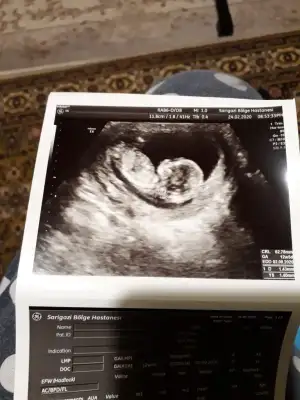

Dr + tam nuba denk getirmiş başka usg varmı12+4 banada yorumlarmisijizIkra meyra

Baska yokDr + tam nuba denk getirmiş başka usg varmı![]()

Dr + tam nuba denk getirmiş başka usg varmı![]()

Bu göre kız ama tutmayabilir tekrar usg olursa paylaşın .usteki 12+3 usg de kafa yapısı kız gibi ama nub göremiyorum .13+ usg olursa paylaşırsınızBaska yok![]()

Bu göre kız ama tutmayabilir tekrar usg olursa paylaşın .usteki 12+3 usg de kafa yapısı kız gibi ama nub göremiyorum .13+ usg olursa paylaşırsınız![]()